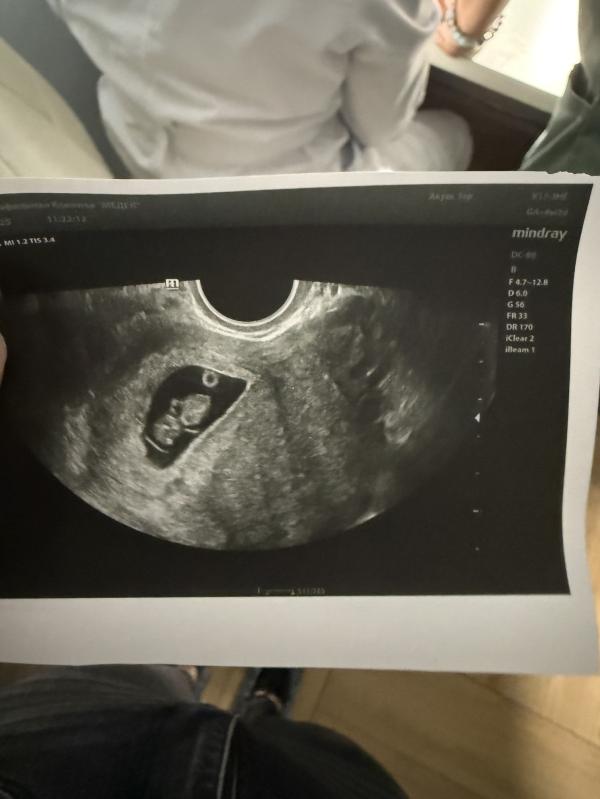

Сказать что я в шоке , не сказать ничего ))

Спасибо )) нет , не планировали , я наоборот больше всех кричала что я больше детей не хочу , нам близнецы дают просраться 😂 у вас наверное тоже весело ?))